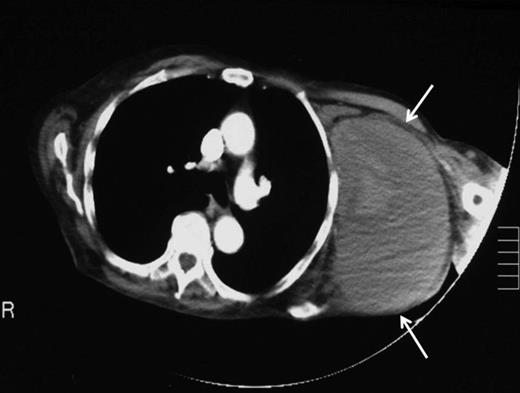

Ten weeks later a repeat orthopaedic review was requested by the rehabilitation team. There had been a slow onset and progression of oedema in the arm, with gradual progression of neurological deficit to the point at which the arm became useless and insensate. An increase in axillary bruising was noted. Also, the patient required a three-unit blood transfusion for a drop in haemoglobin six weeks after the injury. There was a thrill over the whole pectoral region and signs of venous hypertension in the arm. The left radial, ulnar and brachial pulses were normal. Repeat X ray showed subluxation of the left shoulder joint (figure 2). CT angiography revealed a distal axillary pseudoaneurysm with a sac of 15cm diameter (figure 3).

Repeat X-ray of left shoulder demonstrating subluxation of the head of the humerus